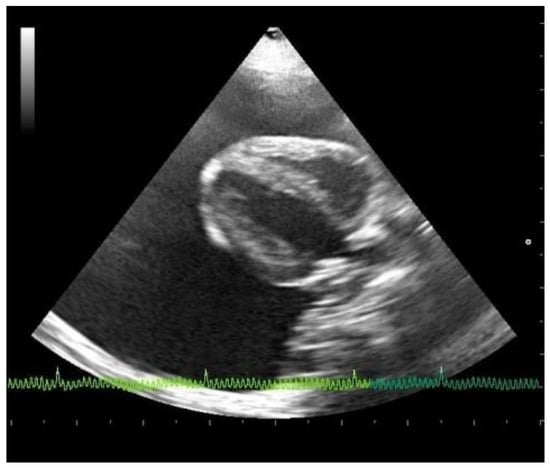

Emergency echocardiography and echo-Doppler examinations, but not a thoracic focused assessment with sonography for trauma (T-FAST) evaluation, were performed, according to the American Society of Echocardiography guidelines, with an Esaote device (My Lab 50 Gold Cardiovascular) and a multifrequency phased-array transducer (7.5–10 MHz) [15]. No echocardiographic reference parameters for this species are reported in the literature, so they have been considered appropriate against those reported in human pediatrics patients of the same weight [16]. Abundant pericardial effusion without diastolic collapse of the right ventricle and no alterations in cardiac morphology were observed, justifying a chronic accumulation of pericardial fluid (Figure 2). A reduction of the fractional shortening, related to the use of alpha two agonist in premedication, was observed [10]. From the cranial to the cardiac base, adhering to the left costal wall at the level of the cranial mediastinum, there was a hyperechogenic neoformation with an inhomogeneous echo structure and irregular margins. Because of the difficulty in reaching the position, and the serious state of dyspnea of the subject, echo-guided, fine-needle cytology was not performed. Pericardiocentesis was performed, at the level of the right hemithorax between the fifth and the eighth intercostal spaces, under echocardiographic control, with drainage of 55 cc of milky whitish, slightly red-tinged, and turbid fluid. The fluid was placed in EDTA-containing tubes. Following pericardiocentesis, the subject developed a slight thoracic effusion, which was no longer present at the ultrasound check after a few weeks.

Figure 2. Echocardiographic right parasternal B-mode evaluation (four chambers view) showing the presence of severe pericardial effusion.